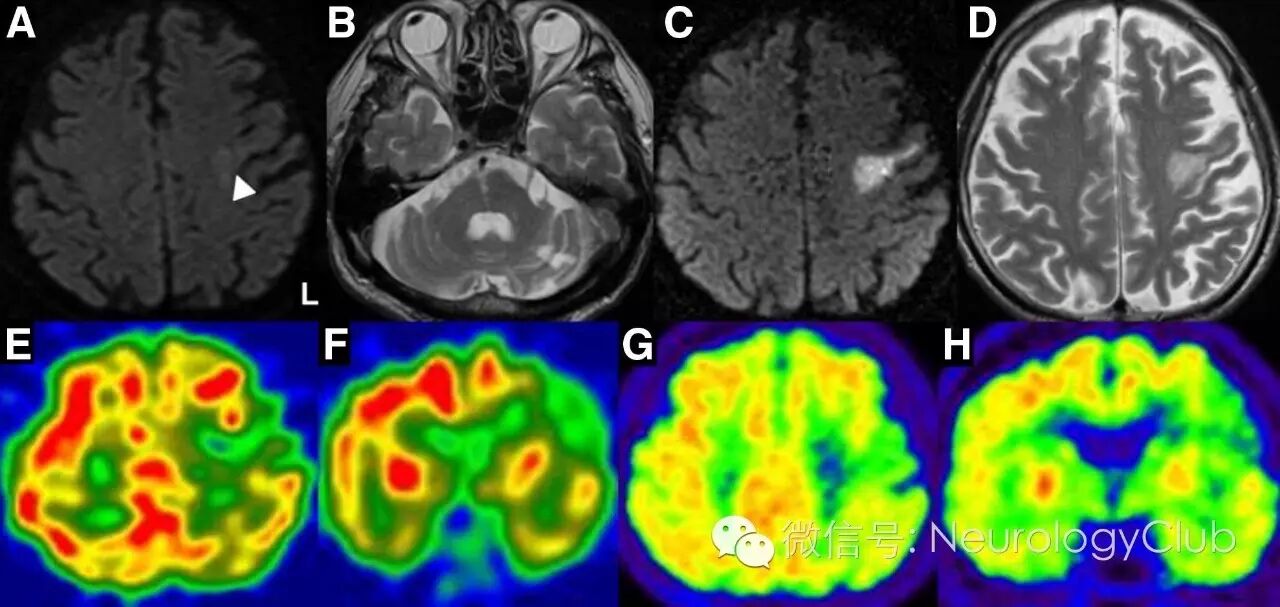

病例2:单侧前岛盖梗死所致的FCMS

(图4:A:起病3小时的DWI可见左侧前岛盖高信号[箭头];B:T2WI提示右侧脑桥和左侧小脑半球陈旧性梗死;C-D:起病第5天的DWI和T2WI提示左侧前岛盖急性梗死;E-H:SPECT和18F-FDG-PET提示新病灶血流减少,葡萄糖代谢降低,对侧半球无明显异常)